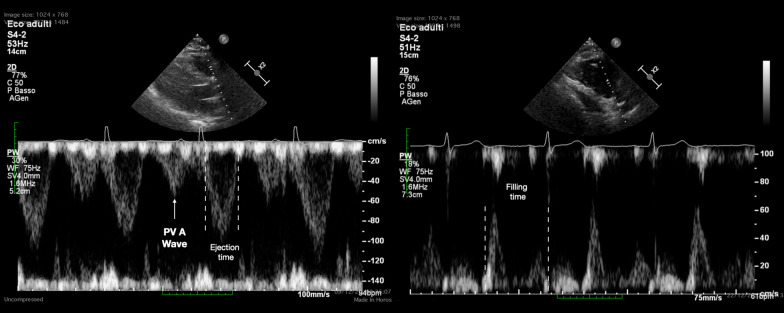

Background: The cardiac manifestations of COVID-19 have been described in patients with acute respiratory distress syndrome (ARDS) admitted to intensive care unit (ICU). The presence and impact of right ventricular (RV) diastolic function and performance has not been studied in this population yet. We describe the prevalence of RV diastolic dysfunction, assessed by the pulmonary valve pre-ejection A wave (PV A wave), and the RV systo-diastolic interaction, using the RV total isovolumic time (t-IVT), in COVID-19 ARDS.

Results: Prospective observational study enrolling patients with moderate to severe COVID-19 ARDS admitted to ICU who underwent a transthoracic echocardiogram within 24 h of ICU admission and at least a second one during the ICU stay. Respiratory, hemodynamic and biochemistry parameters were collected. 163 patients (age 61.0 ± 9.3 years, 72% males) were enrolled. 36 patients (22.1%) had RV dysfunction, 45 (27.1%) LV systolic dysfunction. 73 patients (44.7%) had PV A wave. The RV t-IVT correlated with TAPSE at ICU admission (p < 0.002; r - 0.61), presence of PV A wave (p < 0.001; r 0.78), peak inspiratory pressure (PIP) (p < 0.001; r 0.42), PEEP (p < 0.001; r 0.68), dynamic driving pressure (DDP) (p < 0.001; r 0.58), and PaO2/FiO2 ratio (p < 0.01; r - 0.35). The presence of PV A wave was associated with higher PIP (p < 0.001; r 0.45), higher PEEP (p < 0.001; r 0.56), higher DDP (p < 0.01, r 0.51), and lower PaO2/FiO2 ratio (p < 0.001; r - 0.49).

Conclusions: RV t-IVT and the presence of PV A wave are non-invasive means to describe a significant RV diastolic dysfunction and may be consider descriptive signs of RV performance in COVID-19 ARDS.